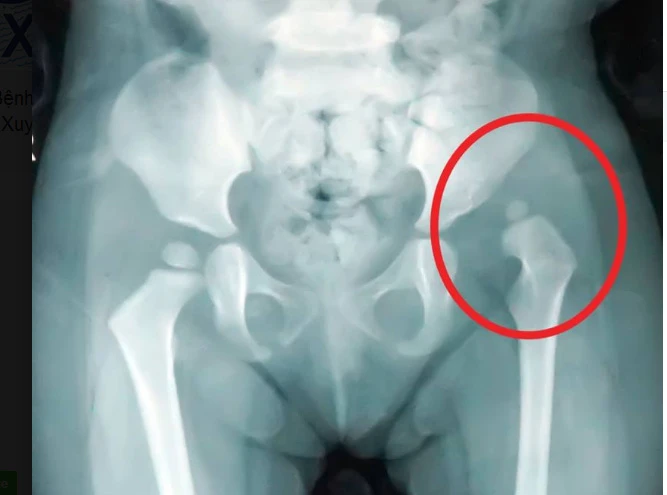

Kết quả chụp X-quang cho thấy bé T. bị trật khớp háng trái bẩm sinh. Ảnh: LÊ PHỤNG

Trước đó, bé T. được đưa vô BV đa khoa Xuyên Á trong tình trạng chân cao, chân thấp khi đi đứng. Kết quả chẩn đoán cho thấy bé bị trật khớp háng trái bẩm sinh nên phải phẫu thuật sớm để tránh các biến chứng nặng về sau.